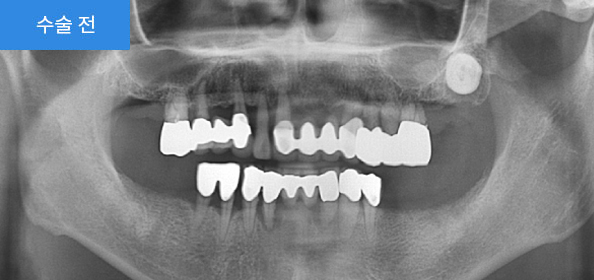

2020.03

어금니가 상실된 상태로 치료를 하지 않은 채 지내시다가 불편함을 느끼셔서 임플란트를 하시게 되었습니다.